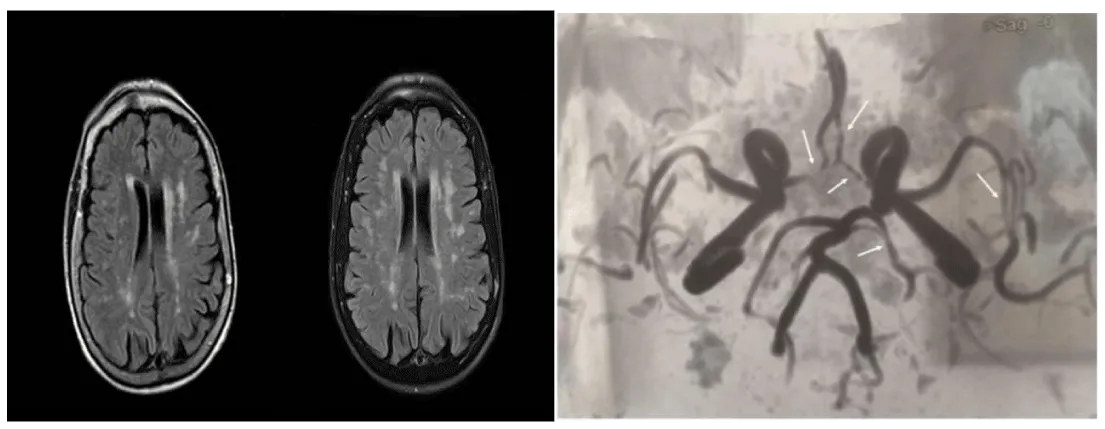

Brain MRI (magnetic resonance imaging) showed multiple patchy lesions, hyperintense on T2 and FLAIR, in the subcortical white matter and in the pons. CSF (cerebrospinal fluid) examination showed no abnormality and oligoclonal bands were absent. MRI of the spinal cord showed enlargement from D6 to D11. The ventral aspect was diffusely hyperintense on D2, with a nonhomogeneous enhancement. A transverse myelitis was hypothesized.

Significant stenoses of medium-small cerebral vessels of both anterior and posterior circulation were detected with magnetic resonance angiography (MRA), thus suggesting the diagnosis of primary angiitis of central nervous system (PACNS). We considered the alternative diagnosis of brain angiitis secondary to systemic disease but we discarded it as the patient had no signs of systemic inflammatory disease and hand X-ray was not compatible with RA.

We treated the patient with prednisone 50 mg/day with rapid clinical and subjective improvement. After one month we reduced prednisone to 25 mg/day. In a few days, the patient reported ageusia, fatigue, and depression. A new MRI showed a progression in number and size of white matter lesions (Figure 1).